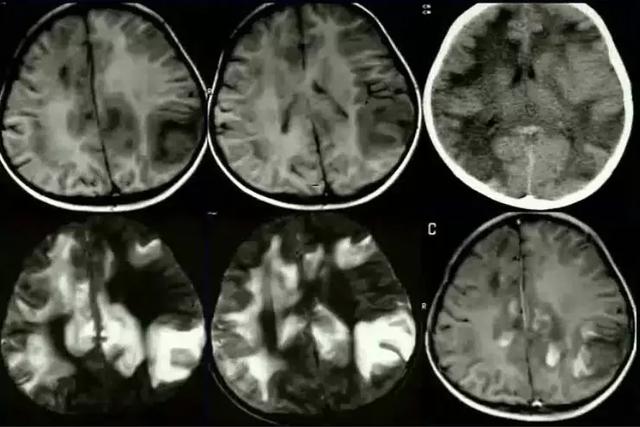

多位于侧脑室旁白质、半卵圆中心、也可位于脑干、颅神经等处,灰质核团受累少见,国人好发于脊髓、视神经

病灶呈卵圆形,沿侧脑室放射状分布,呈「垂直征」,长 T1、长 T2 信号,中心可囊变,活动期增强明显,静止期无增强,活动期 DWI 呈高信号